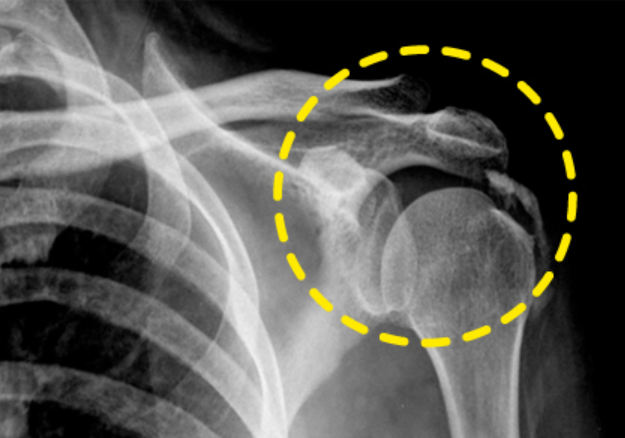

대부분 어깨통증은 50대 이후에서 생기지만 최근에는 여러 이유로 젊은 연령층에서도 많이 생기고 있습니다. 그 중 하나가 바로 어깨 석회질인데 어깨 인대가 탄력을 잃으며 칼슘 성분인 석회가 회전근개 힘줄 내에 쌓이는 질환으로 석회성 건염이라고 부릅니다.

우리가 흔히 힘줄이라고 하는 부위는 회전근개 힘줄을 의미합니다. 석회 성분 대부분은 칼슘이 축적되면서 침전물이 커지면서 자극과 통증을 유발합니다. 힘줄 내부에 석회가 갑자기 분해가 되는데 이 때 견봉하의 점액낭으로 떨어져 나가며 염증 반응을 유발해 통증이 챙기는 것으로 알려져 있습니다.